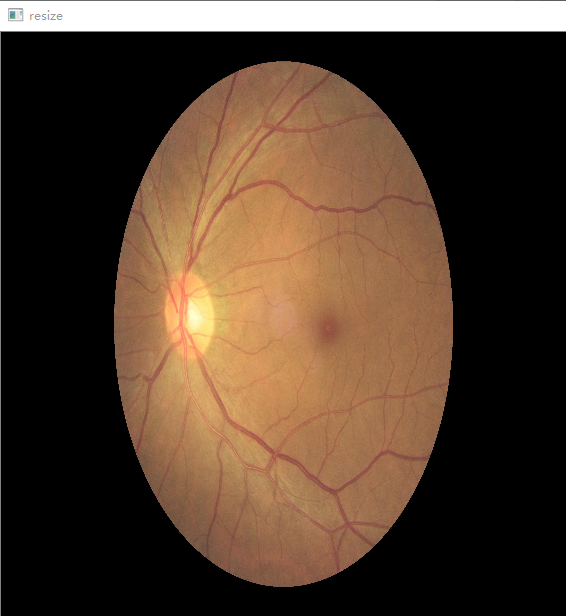

对眼底图像中心区进行血管的检测。用了HoughLinesP()直线检测法,附上执行时的三张图

img_resized = cv2.resize(img_ori, (width, height), interpolation=cv2.INTER_CUBIC)

cv2.imshow('resize', img_resized )